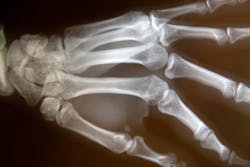

A clinical trial at the National Institutes of Health found that a medication, denosumab, significantly reduced abnormal bone turnover in adults with fibrous dysplasia, a rare disease marked by weak and misshapen bones.

Bone turnover, a process in which old bone is continuously replaced with new bone, is unusually accelerated in fibrous dysplasia and contributes to bone abnormalities. The study of eight participants was carried out by researchers from the National Institute of Dental and Craniofacial Research (NIDCR) and the NIH Clinical Center. The results, which showed that denosumab may improve patients’ quality of life by enabling healthy bone formation, were published as a correspondence report in the New England Journal of Medicine.